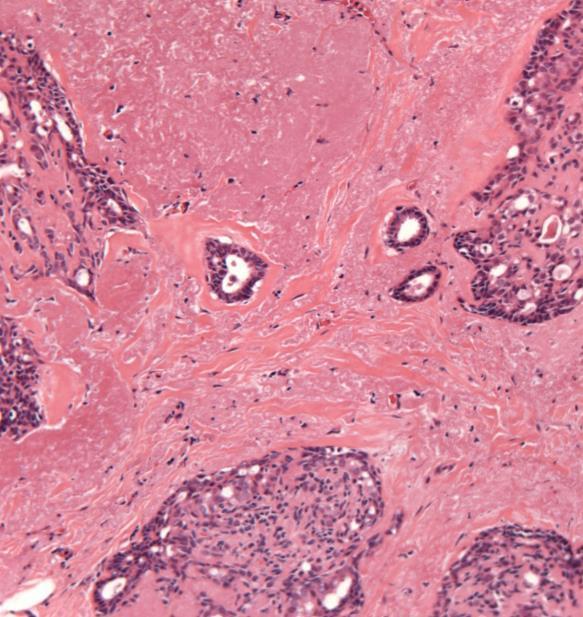

Case 7

◼ Invasive ductal NST carcinoma, grade 1

◼ Sclerosing adenosis

Case 11

◼ Radial scar.

◼ No atypia or malignancy.

◼ Radial scar/complex sclerosing lesion:

Architecture

Fibroelastotic stroma preserved myoepithelium

No epithelial atypia

DD

Tubular Carcinoma/grade 1 carcinoma

◼ Absent myoepithelium

◼ Desmoplastic stroma

◼ Epithelial atypia

Radial scar

◼ On core biopsy: B3

◼ Comment on presence/absence of atypia

◼ Second line VAB (VAE)